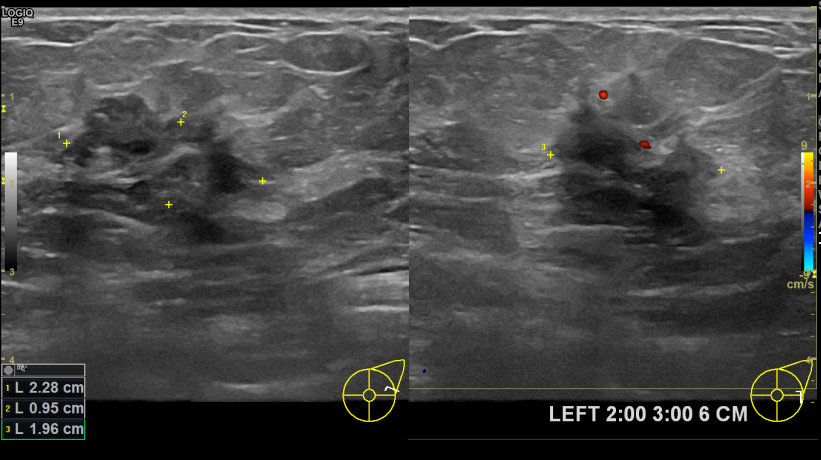

아산유외과개원후 743번쨰 유방암진단

상기환자 외부검진상 이상소견으로 조직검사권유받고 내원하신 50대 여성분으로 좌측유방멍울 조직검사 시행 후 유방암 진단되었습니다.